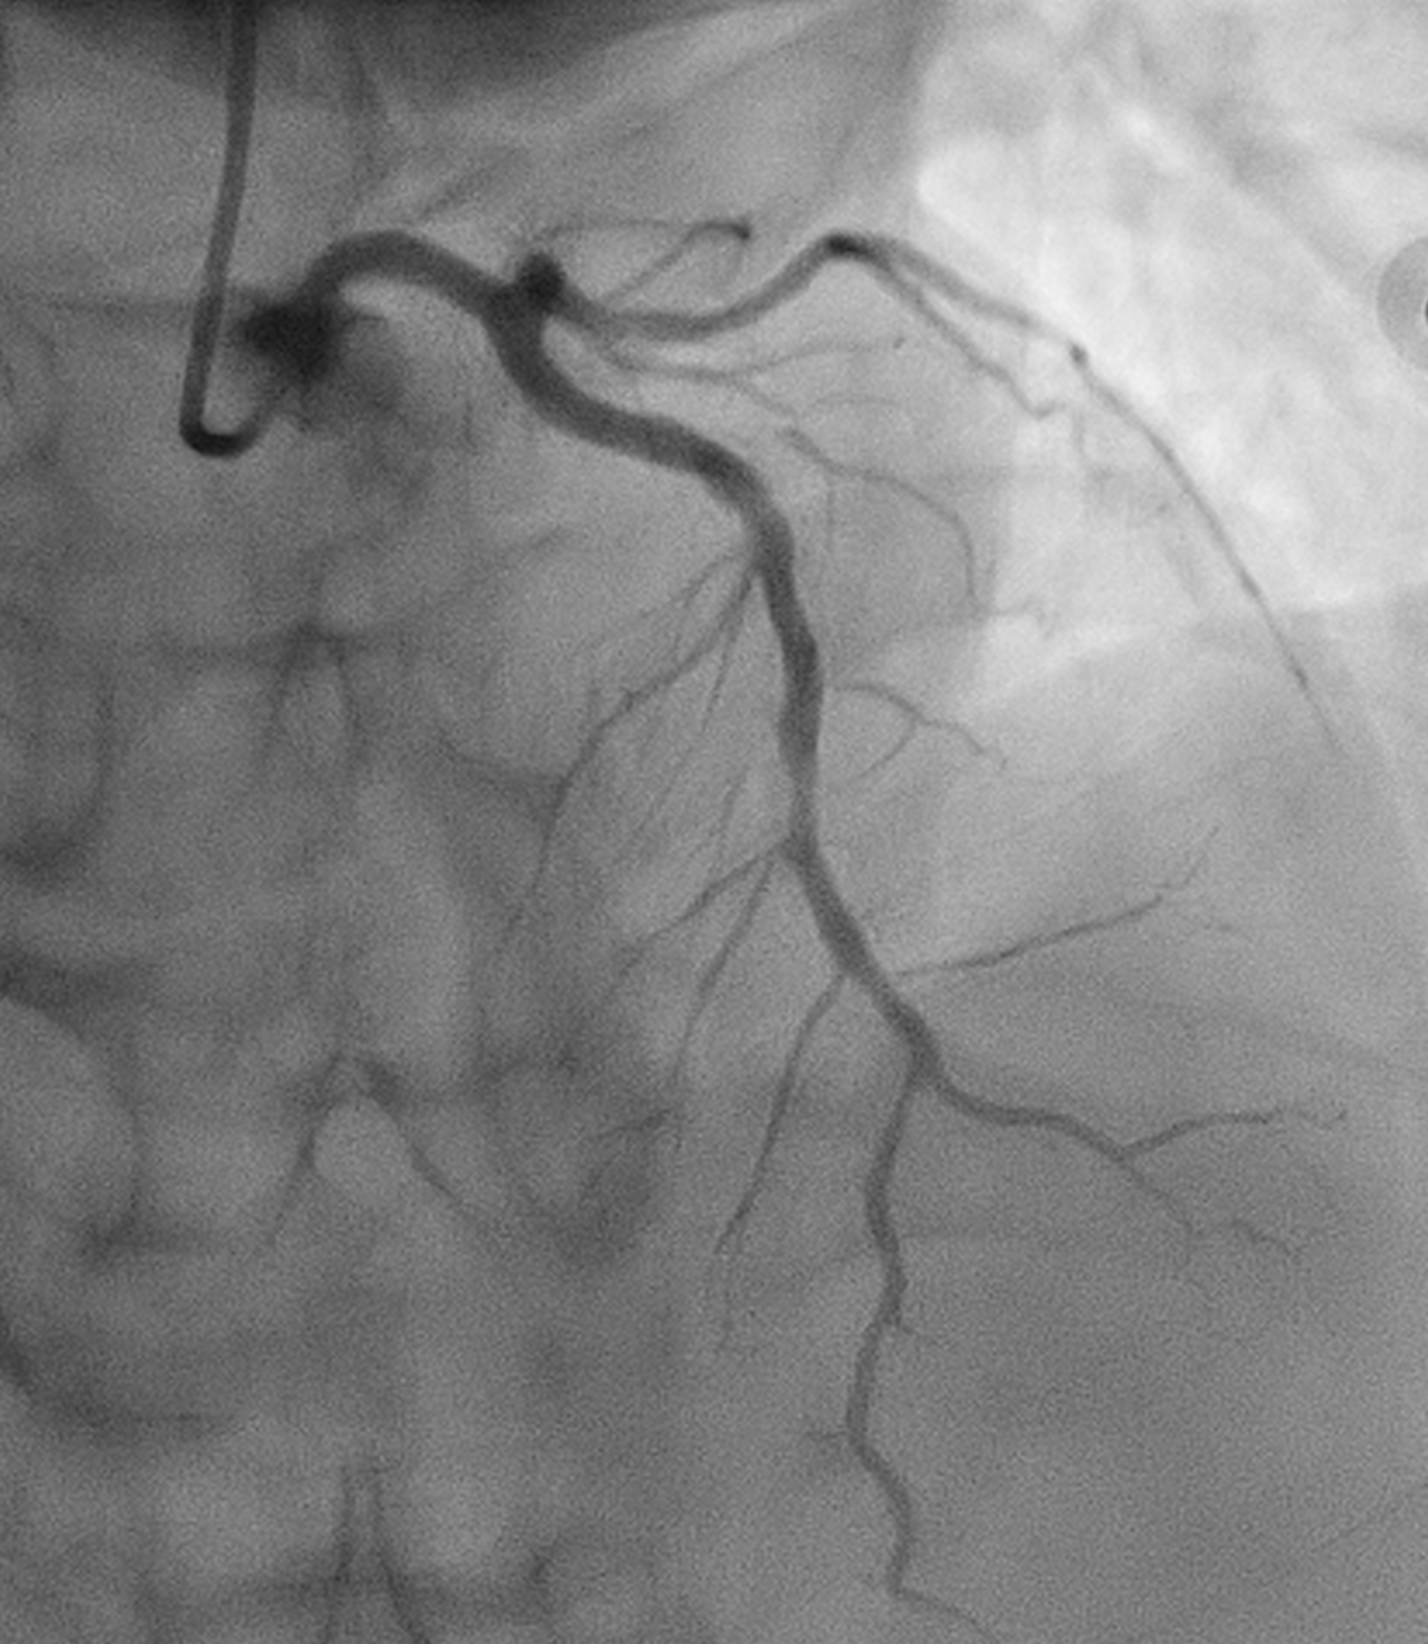

WE DECIDED TO INTERVENE THE CTO MLAD IN VIEW PERSISTENT ANGINA. BILATERAL RADIAL ARTERY PUNCTURE, WITH ANTEGRADE APPROACH. WE ENGAGED RIGHT CORONARY ARTERY WITH JR4 6 FR AND WIRED DOWN WITH RUNTHROUGH FLOPPY. ENGAGED THE LEFT CORONARY ARTERY WITH EBU 3.5 7FR. INITIALLY TRIED TO WIRE THE LAD WITH FINECROSS MICROCATHER (MC) USING SION BLACK WIRE BUT FAILED. SUBSEQUENTLY CHANGED TO GAIA 1ST AND MANAGED TO CROSS SUCCESSFULLY. IVUS SHOWED 360 DEGREE CALCIFICATION WITH 270 DEGREE CALCIFICATION MORE THAN 5 MM, IVUS CALCIUM SCORE 2. CALCIUM DEBULKING WAS DONE USING ROTABLATION WITH 1.5 BURR RUN 3 TIMES AT 220 KRPM FOR 10 SECS AND POLISHING RUN TWICE AT 140 KRPM. POST ROTA SHOWED PRESENCE OF FRACTURED CALCIUM WITH REVEBERATION SIGN. LESIONS WAS PREPARED FURTHER USING WOLVERINE 3.0 X 10MM AND 3.5 X 10MM. POST CUTTING BALLOON SHOT SHOWED NO DISSECTION, TIMI 3 FLOW AND RESIDUAL STENOSIS 30%. DECIDED FOR DCB WITH PANTERA LUX 3.0 X 20MM AND AGENT 3.50 X 30MM. FINAL SHOT SHOWED TIMI3 FLOW, NO DISSECTION SEEN. PATIENT REMAIN ASYMPTOMATIC AT 6 MONTHS AND REPEATED COROS SHOWED MODERATE STENOSIS AT MLAD WITH NEGATIVE FFR (0.92).

Case Summary